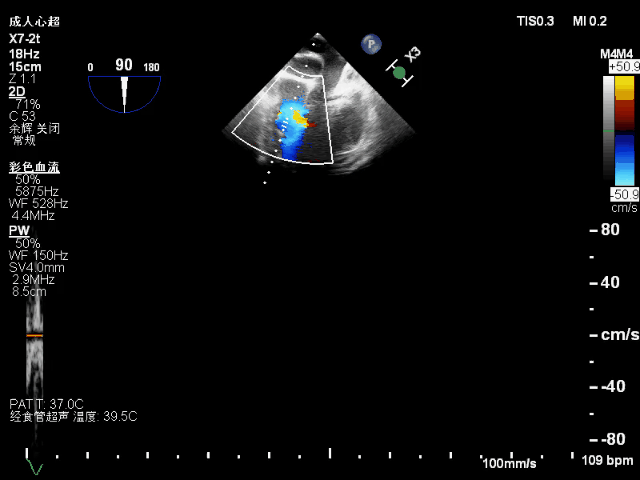

术后